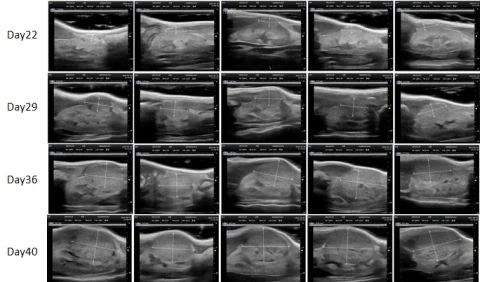

PDX Model (Growth Curve)

部分beats365PDX原位模型展示

部分beats365PDX原位模型展示